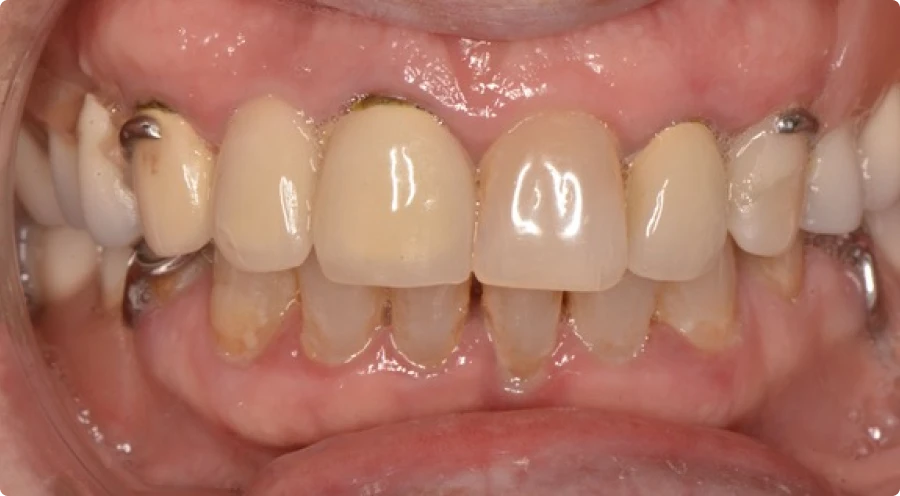

Pour illustrer l’impact de nos traitements, voici quelques exemples concrets de réhabilitations globales réalisées au cabinet Horizon Sourire. Ces cas cliniques montrent différentes situations où des traitements multidisciplinaires ont permis à nos patients de retrouver une santé dentaire optimale. Chaque photo présente l’évolution avant et après les soins, mettant en évidence les résultats fonctionnels et esthétiques obtenus. Ces exemples démontrent notre approche globale, personnalisée et coordonnée, visant à restaurer la mastication, améliorer l’apparence du sourire, et renforcer la confiance de nos patients. Découvrez ces transformations qui témoignent de notre engagement à offrir des soins dentaires de qualité.